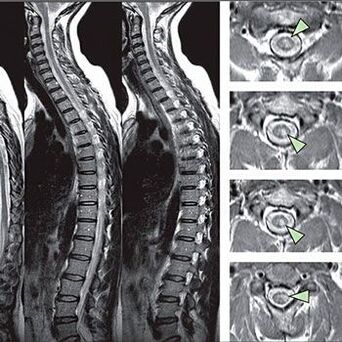

Méthodes pour diagnostiquer l'ostéochondrose de la colonne thoracique

Pour identifier les signes de troubles de sensibilité, des tests fonctionnels spéciaux sont effectués. L'option la plus informative pour le diagnostic des méthodes instrumentales est la performance d'une x-rayons. Cependant, pour une étude exhaustive de la colonne vertébrale, la résonance magnétique et le TC sont souvent réalisées. En cas de suspicion de maladies du système cardiovasculaire, le patient est recommandé de se soumettre à la procédure ECG.